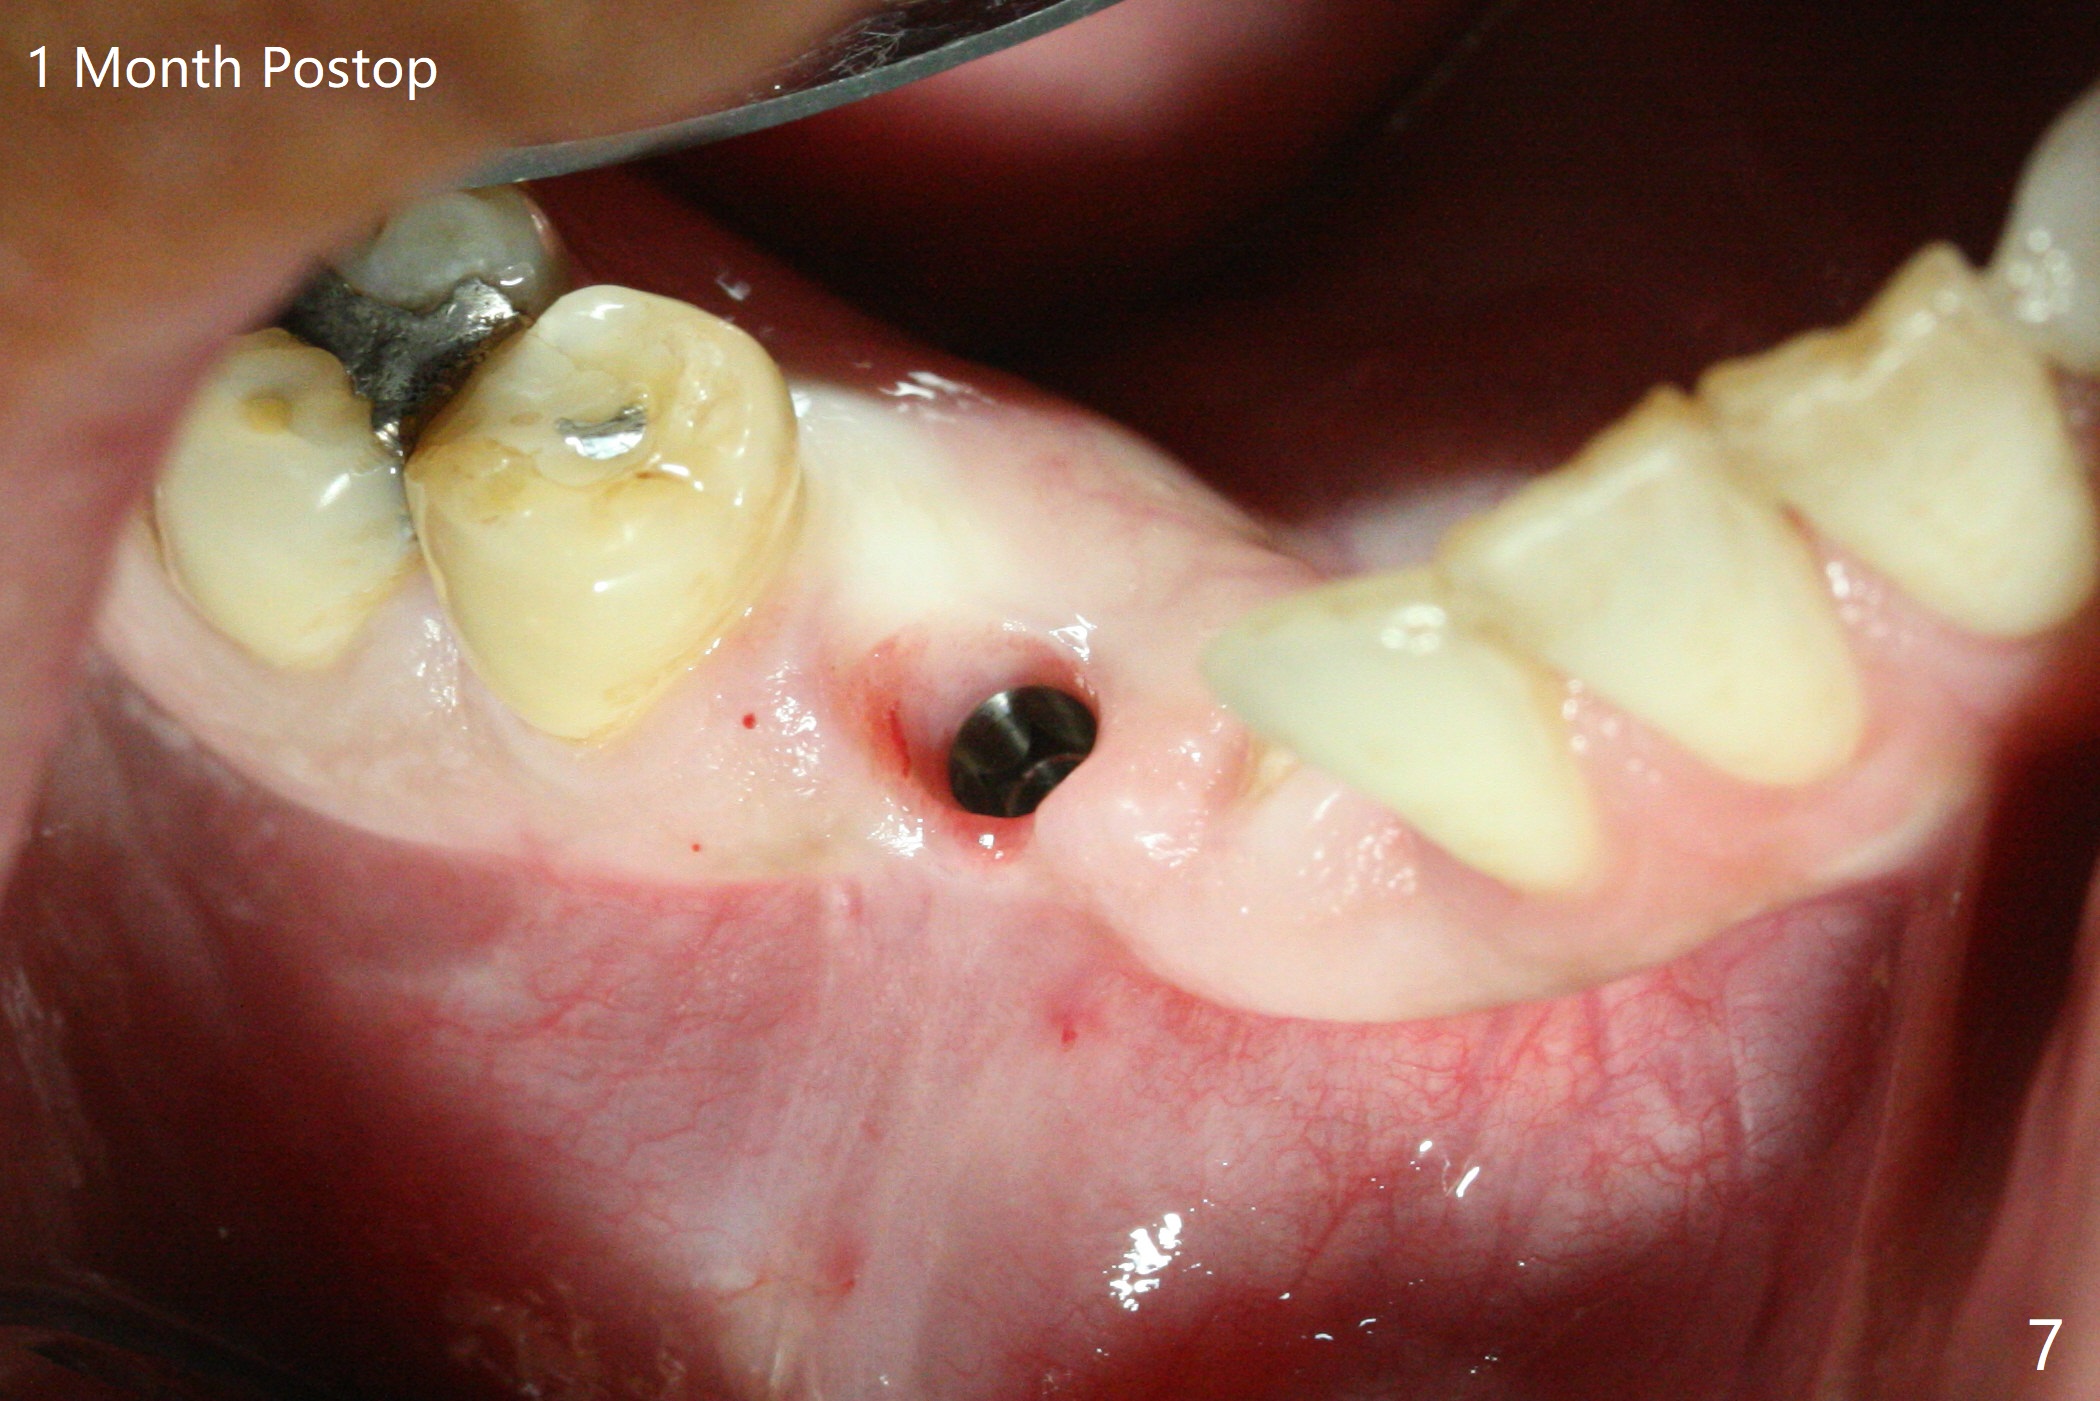

When the surgical guide for #28 is removed, the 4x13 mm implant is found to be superficial and buccal. Part of the buccal mucosa is nonkeratinized. After 1 mm deeper placement of the implant, CT confirms the buccal placement (Fig.1, as compared to design). In fact the guide was doubly checked for fitness prior to osteotomy, but grossly it seemed to be seated properly. The suspicion is related to the trimming at the site of #27 (Fig.2,3 (*), as compared to a mounted model in Fig.4,5 (arrowhead) and the model sent to lab for guide fabrication). The lab agrees to redesign the case. There is a narrow buccal band 1 week postop (Fig.6). The patient is a smoker. The implant was placed buccal (Fig.7, 1 month postop). A new 4x13 mm implant is placed on the top of the 1st line following 3x14.5 mm drill (Fig.8 (35 Ncm)). In fact the implant position is not changed much. Four months post banding (20 ss) and 2 months post 2nd implant placement, the tooth #27 is exposed for bracket; extrusion is initiated (Fig.9). In 3 weeks of retraction, the bracket is supragingival (Fig.10). The canine contacts the distal healing abutment with 2 months of retraction (Fig.11). It seems necessary to initiate lower bracket placement. There is no bone loss 4 months postop (Fig.12). A 4.5x7(4) mm abutment is placed (Fig.13) for a temporary crown as an anchor (Fig.14) to further extrude #27 with continuous inter-arch retraction (to reduce tension upon #26 with severe bone loss (Fig.12)). LR3 extrusion is incomplete, although there is an increase in bone distal to LR2 ~ 10 months of extrusion (Fig.15).